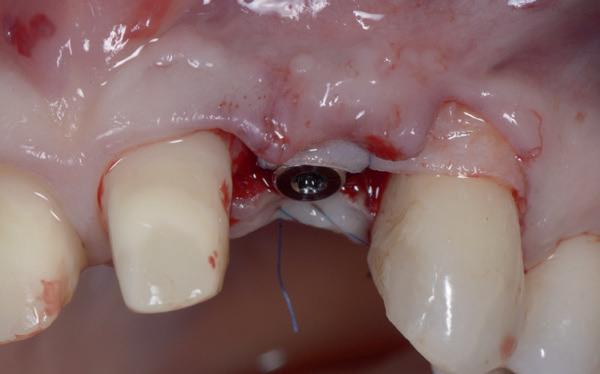

Tijdens het verwijderen van het membraan is het botvolume klinisch waarneembaar en blijkt dat er voldoende bot is om het implantaat te kunnen plaat-

sen. Tijdens deze procedure wordt er ook een free gingival graft van het palatum gehaald. Deze wordt buccaal aangebracht van de 22 en 23 om zo de recessie zoveel mogelijk te bedekken en de papil tussen de 22 en 23 van meer volume te voorzien.

De flap en graft worden met poly-propelene 6.0 hechtingen gefixeerd. De tijdelijke reconstructie wordt herplaatst (foto 17-20).